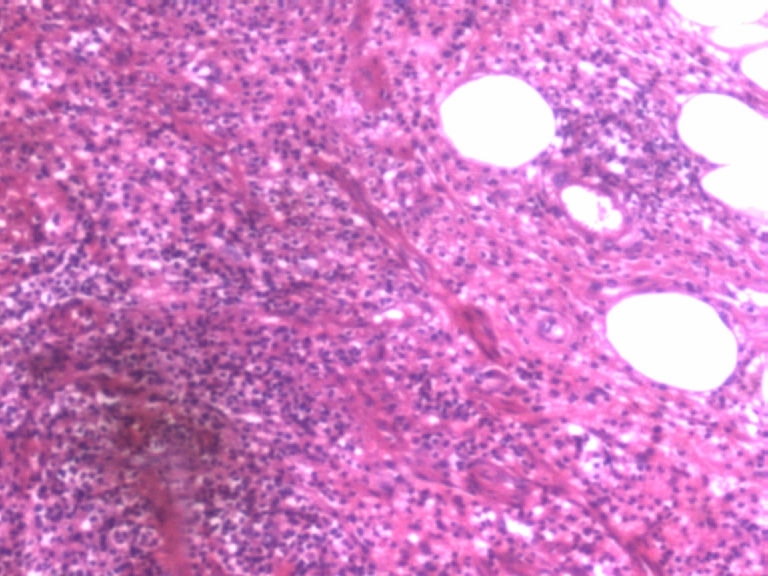

男,50岁,阑尾长7厘米,直径0.4---0.6厘米。剖开:尖端看见淡黄色区,不规则,界限欠清,0.15*0.2厘米,质中。

• 您看了吗?阑尾类癌?图4

图4

考虑阑尾类癌

按照胃肠胰腺神经内分泌肿瘤WHO2010分类,该例应属于NET G1(神经内分泌瘤,1级)。需标记Syn, CgA, Ki67.

倾向神经内分泌肿瘤,建议做CgA、SYN、Ki-67检查。

阑尾的神经内分泌肿瘤我们已经碰到好几例了,一般都在阑尾尖端,取材一定要规范,这样可以减少漏诊率。